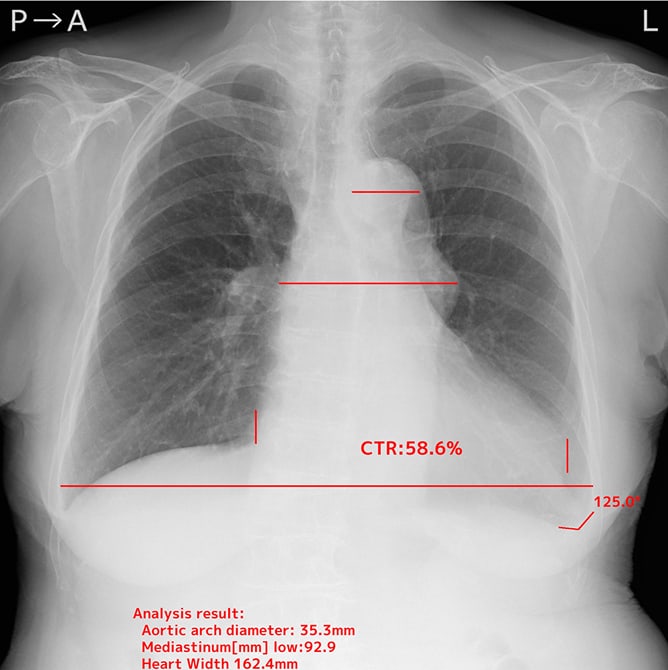

- 心胸郭比

- 縦隔幅(上部、中部、下部)

- 大動脈弓の径

自動計測機能